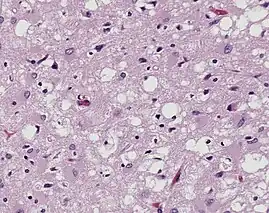

Magnified 100× and stained. This photomicrograph of the brain tissue shows the presence of the prominent spongiotic changes in the cortex, with the loss of neurons in a case of a variant of Creutzfeldt-Jakob disease (vCJD)

Prions are misfolded proteins that transmit their abnormal folding pattern to other copies of the protein without using nucleic acids. Besides obtaining prions from others, these misfolded proteins arise from genetic differences, either due to family history or sporadic mutations.[21] Plants uptake prions from contaminated soil and transport them into their stem and leaves, potentially transmitting the prions to herbivorous animals.[22] Additionally, wood, rocks, plastic, glass, cement, stainless steel, and aluminum have been shown binding, retaining, and releasing prions, showcasing that the proteins resist environmental degradation.[23]

Prions are best known for causing transmissible spongiform encephalopathy (TSE) diseases like Creutzfeldt–Jakob disease (CJD), variant Creutzfeldt–Jakob disease (vCJD), Gerstmann–Sträussler–Scheinker syndrome (GSS), fatal familial insomnia (FFI), and kuru in humans.[24]